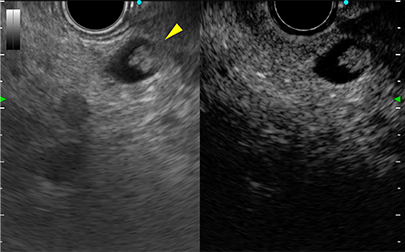

膵尾部分枝型IPMN

超音波内視鏡のみでのう胞内結節を指摘

急性胆嚢炎で受診

超音波内視鏡下胆嚢ドレナージ

十二指腸から

胆嚢にステント留置